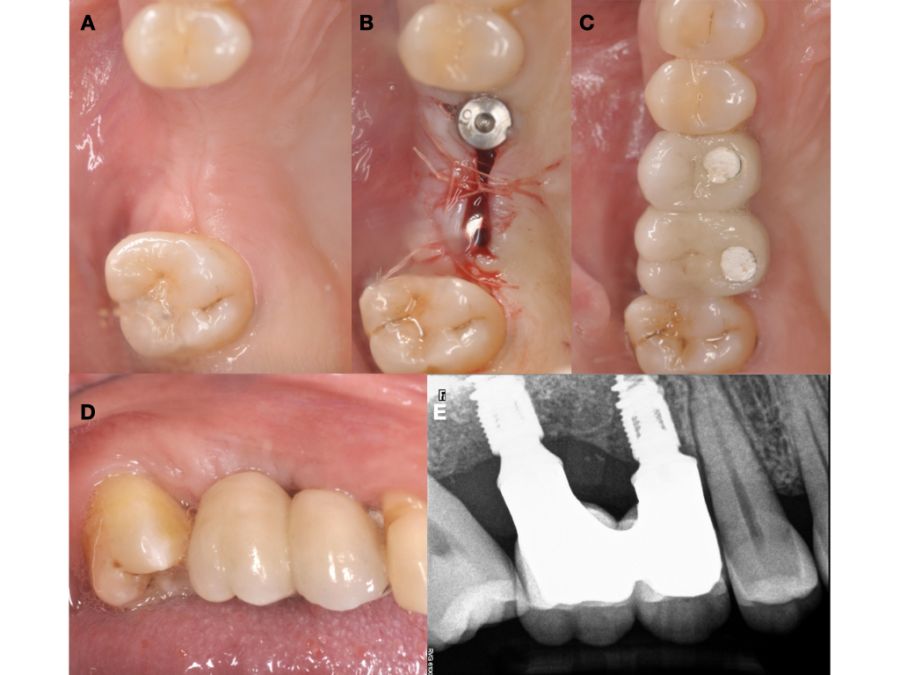

Se planificó la exodoncia del 4.8 para utilizarlo como diente donante, para lo que se firmó previamente el consentimiento informado. Se realizó un bloqueo anestésico mediante articaína (Inibsa®, Barcelona, España) al 4% con adrenalina 1:100.000 del nervio dentario inferior, del nervio lingual y, por último, del nervio bucal. Al ser un diente sin procesos infecciosos asociados, únicamente se eliminó del diente el cálculo mediante instrumental ultrasónico y se realizó la extracción de la forma más atraumática posible. Se pulió la superficie radicular con fresas de diamante de turbina con abundante irrigación, eliminando de esta forma el ligamento periodontal (Figura 3).

Durante el tiempo de preparación del diente en el dispositivo Tooth Transformer® se realizó la elevación de seno de acceso lateral mediante un bloqueo anestésico con articaína 4% con adrenalina 1:100.000 (Inibsa®, Barcelona, España) del nervio alveolar superior posterior y medio, y el nervio palatino mayor. Tras una incisión de Neumann parcial con una descarga vertical en la línea ángulo mesial del 1.5, se realizó el despegamiento mucoperióstico y mediante el sistema Sinus Master III® (MCTBIO, Gyeonggi-do, 17037, Corea del Sur) se realizó una osteotomía de forma controlada usando un sistema de presión hidráulica y fresas diamantadas. Se colocó el injerto de diente procesado en el interior del seno maxilar y se colocó una membrana reabsorbible de colágeno Lyoplant® (B. Braun Medical S.A, Barcelona, España) cubriendo el injerto. Tras este paso, se suturó con sutura monofilamento no reabsorbible de 4/0 (Supramid®, B. Braun, Barcelona, España) (Figuras 5 y 6).

Seis meses tras la cirugía de elevación de seno maxilar se realizó la reentrada para la colocación de implantes. Se obtuvo una biopsia de tejido óseo de 3 x 7 mm mediante trefina y se solicitó un análisis histomorfométrico, obteniendo un 30,56% de hueso vital (Figura 7). Tras la muestra para la biopsia se colocaron dos implantes bone level Naturactis de ETK® (ETK Implants S.L, Sant Boi de Llobregat, España) con un torque de inserción de 35 Ncm, comprobándose su correcta colocación en el postoperatorio inmediato mediante una radiografía periapical (Figura 8). Seis meses tras la colocación de los implantes la paciente pudo acudir a realizarse la segunda fase para colocar pilares de cicatrización, y mediante un CBCT de comprobación se valoró la altura ósea final, teniendo un incremento de 4,2 mm en la zona del 1.6, y de 6,1 mm en la zona del 1.7 (Figura 9).

Quince días después de la segunda fase se realizó la toma de impresiones para la realización de dos coronas ferulizadas cemento-atornilladas sobre bases de titanio, comprobándose el ajuste mediante una radiografía periapical paralelizada (Figura 11). Seis meses tras la colocación de la restauración se realizó una revisión clínica y radiográfica, observando el buen aspecto de los tejidos blandos (Figura 12).